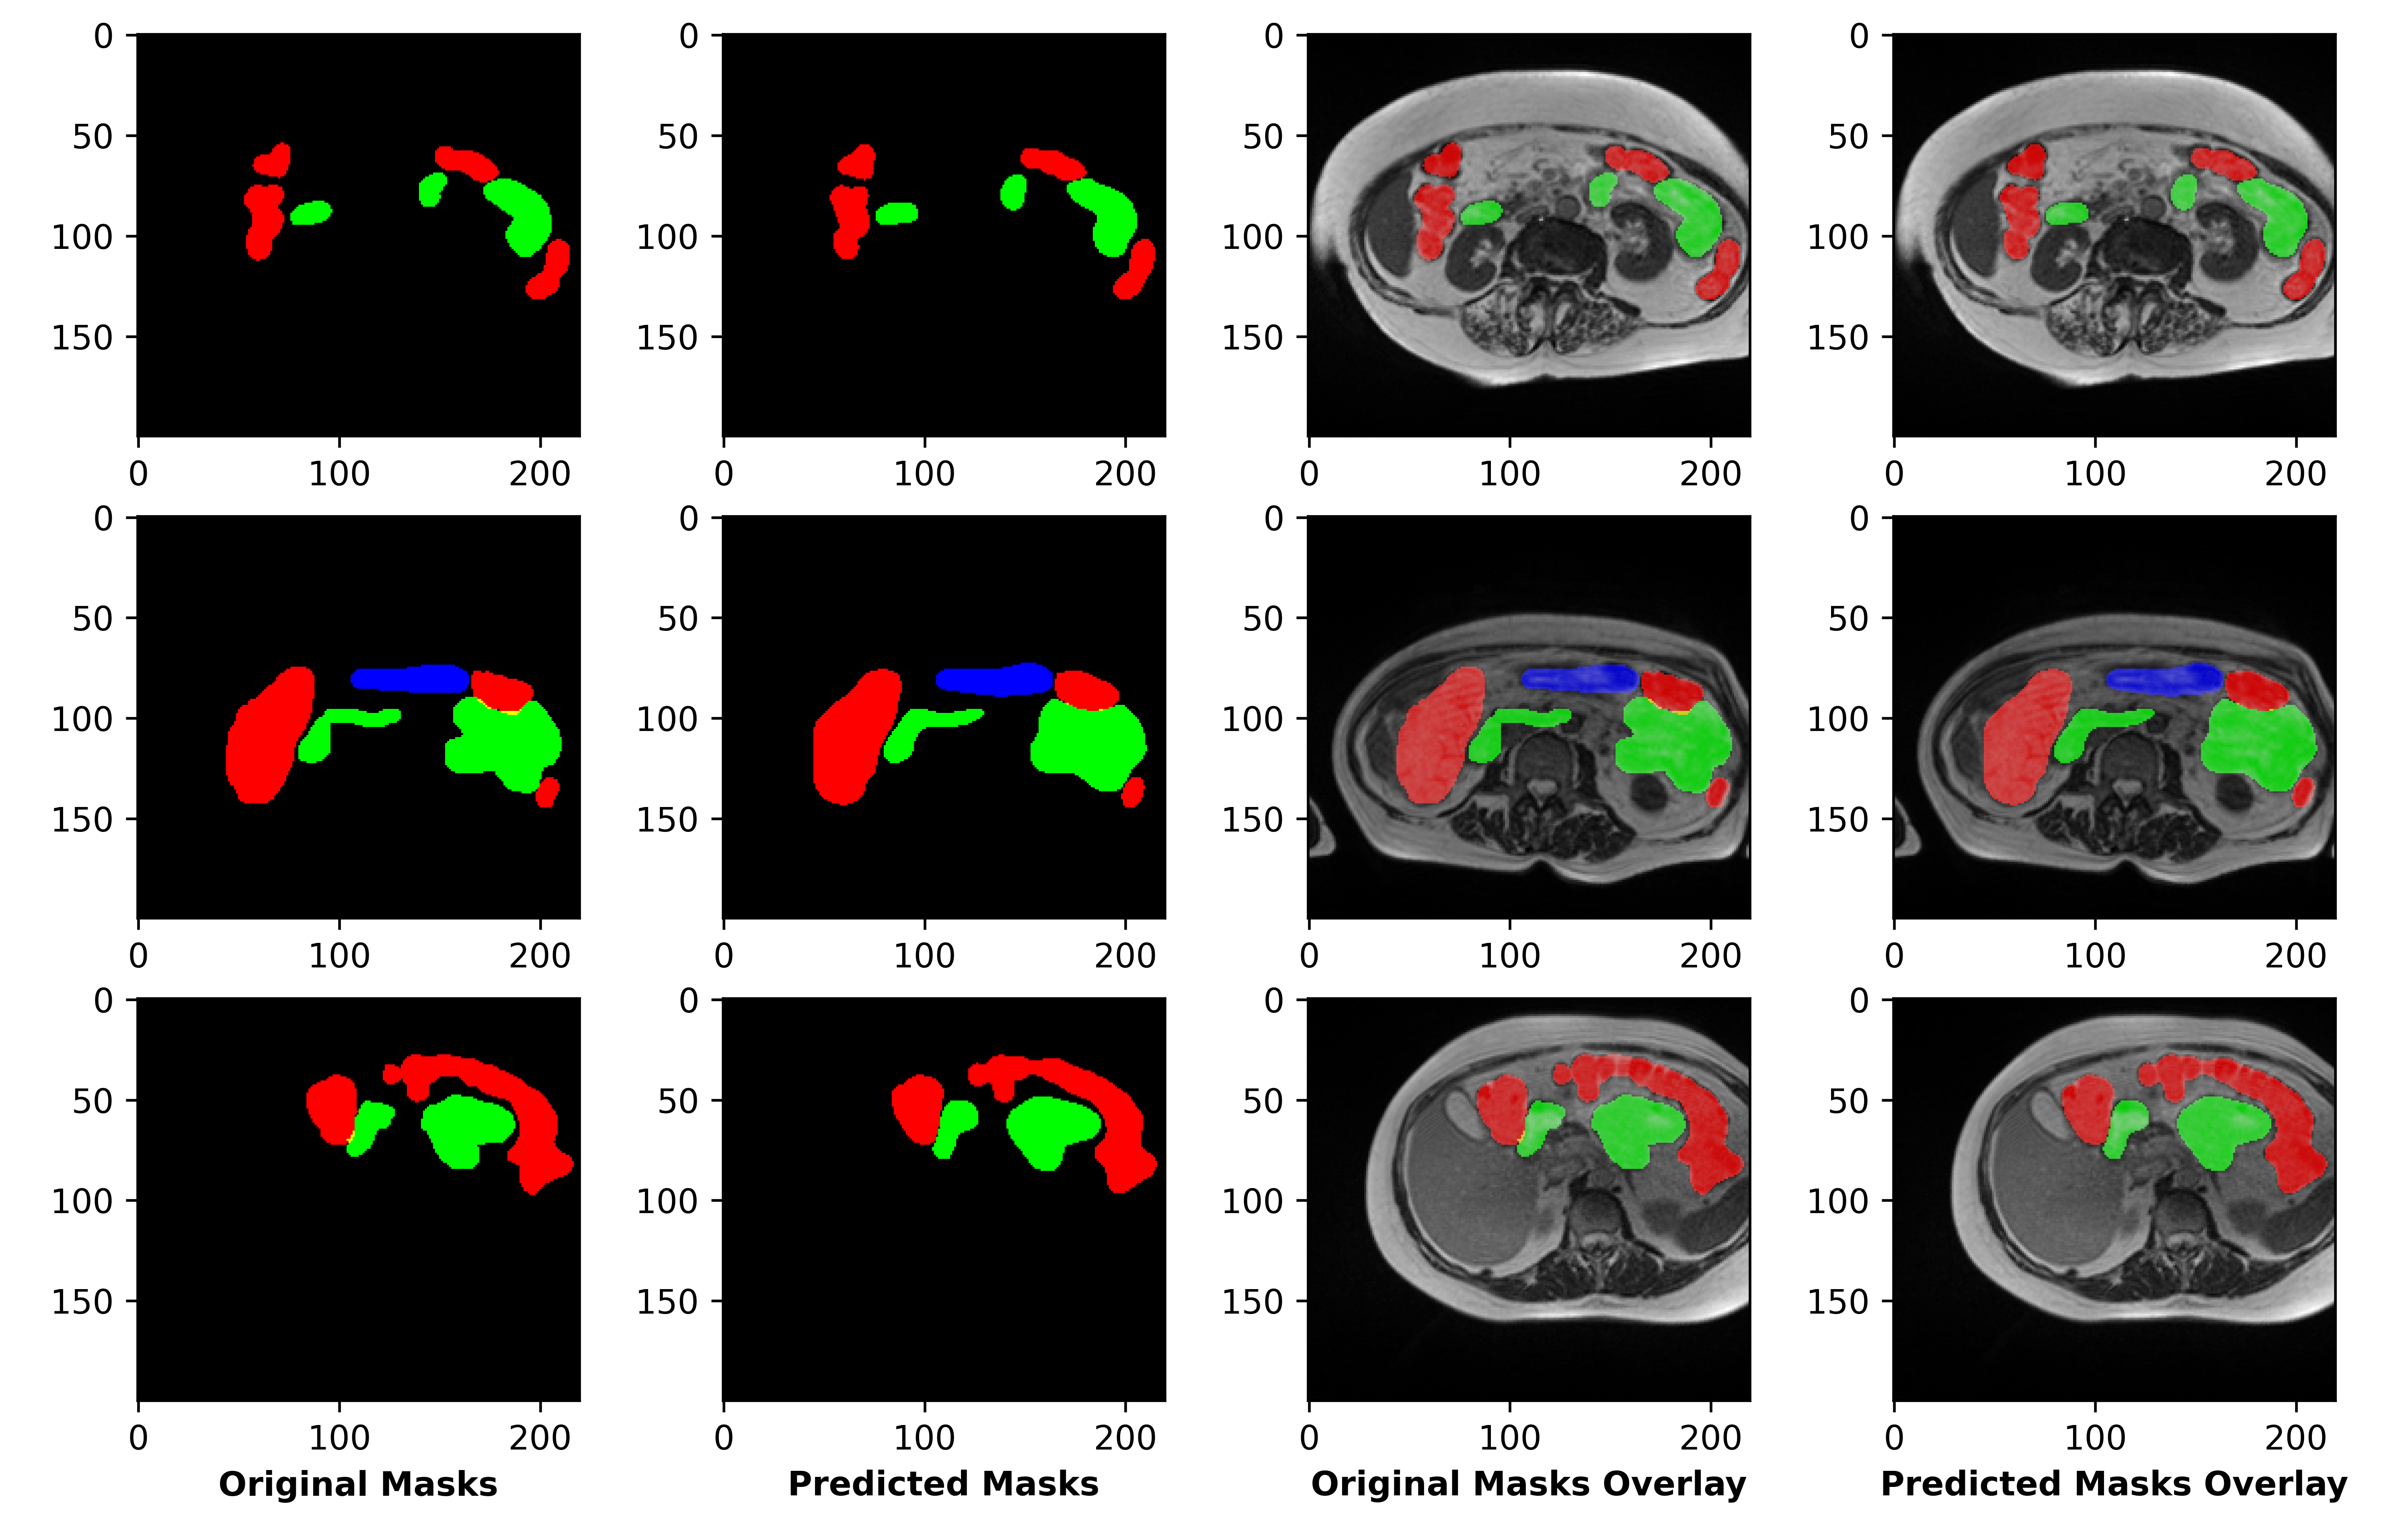

Refer to caption

Figure 5: Final Predictions after training